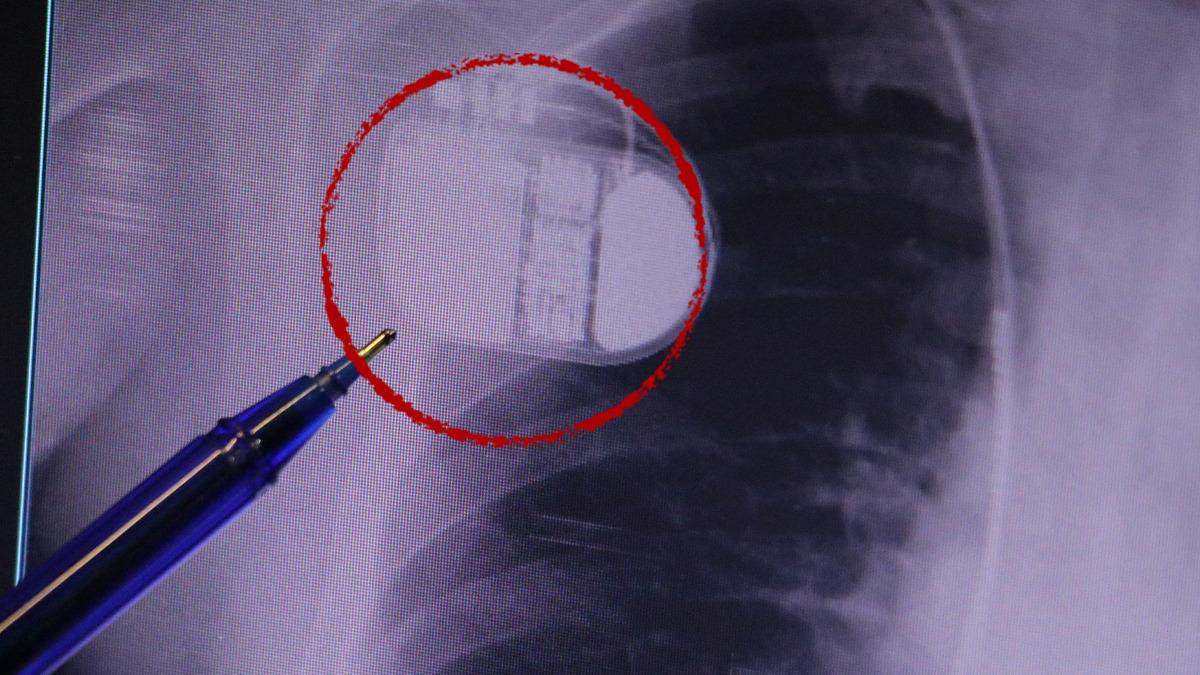

Kalp krizleri sonrası kalp dokusunun zarar gördüğünü söyleyen İsmail Erdoğu, "Dünyada artık kalp hastalıkları en sık ölüm sebeplerinden biri. Kalp hastalıklarında çok fazla grup var. Biz kalp hastalıkları deyince sadece kalbinde stent olan ve damarlarında sorun bulunan insanlardan bahsetmiyoruz. Aynı zamanda tansiyon ve şeker hastaları da kalp hastalıklarına aday. Toplumun yaklaşık yüzde 30-35'lik bir kısmını kapsıyoruz. Çok yaygın bir hastalık ve bu hastalıkta teknolojik kapsamda, ilaç konusunda son 30 yılda çok ciddi gelişmeler oldu. Geçmişte insanları hastanelerde kalp krizinden dolayı kaybederken şimdi hastaneye başvurular sonrasında yaşama tutunmak büyük oranda mümkün. Yaşanan ölümler ise genellikle hastaneye gelmeden önce gerçekleşmekte. Kalp krizinden kurtulmanın hastalarda belli bir bedeli oluyor. Kalp krizi sonrası kalpteki dokular zarar görüyor ve kalp yetersizliği oluşuyor. Bu kalp yetersizliği olan kalplerde ritim bozuklukları ve ani ölümler gibi sorunlar gündeme gelebiliyor. Bunlardan uzun vadede korunmak için hastalarda mutlaka bir kalp piline ihtiyaç duyuluyor" dedi.

Kalp pilleri ile MR cihazına girilebileceğini belirten Erdoğu, "Çok büyük bir ameliyat değil ama yine de ciddi bir cerrahi işlem. Kalp pili, tıpta son 30 yılda yaşanan gelişmelerden en büyüğü. Bir bilgisayarın küçültülüp insan vücuduna konulmuş hali aslında. İnsan ömrünü ciddi oranda uzatan bir tedavi. İnsanlar bir şokla hayata tutunurken, pil olmasaydı öleceğini düşündüğümüz birçok hastamız var. Kalp pilinin bu özelliği, uygun hastalarda ciddi oranda ani ölümü engelliyor. Hastanın başına gelecek bir kalp durması durumunda yanında bir sağlıkçı yoksa, onun ritmini düzeltecek defibrilatör cihazı yoksa hastayı hayatta tutmak mümkün değil. Uygun endikasyonlarda kalp pili olduğu zaman, pil hastaların ritmini algılıyor ve acilde yapılan şoklamayı yaparak hastayı hayata döndürüyor. Kalp pillerinde yeni teknolojilerle MR'a girmek mümkün, tomografiye zaten girebiliyorlar. Tarama cihazlarından geçmelerini uygun görmüyoruz. Bu tarz durumlarda hastalarımız 'kalp pilim var' dediğinde muaf tutuluyorlar. Kalp pilleri ciddi teknolojik cihazlardır. Vücudun içindeki titreşimi, örneğin mikser kullanmak, kolunu sallayacak herhangi bir eylem kalp pilinde olumsuz etki oluşturabilir. Soğuk havalarda vücutta oluşan ciddi titremeler kalp pilinin hafızasını karıştırıp kalbin durduğunu düşündürebilir ve gereksiz şoklama yapabilir. Bu tarz kişilerin soğuk havalarda daha temkinli olması gerekir" dedi.